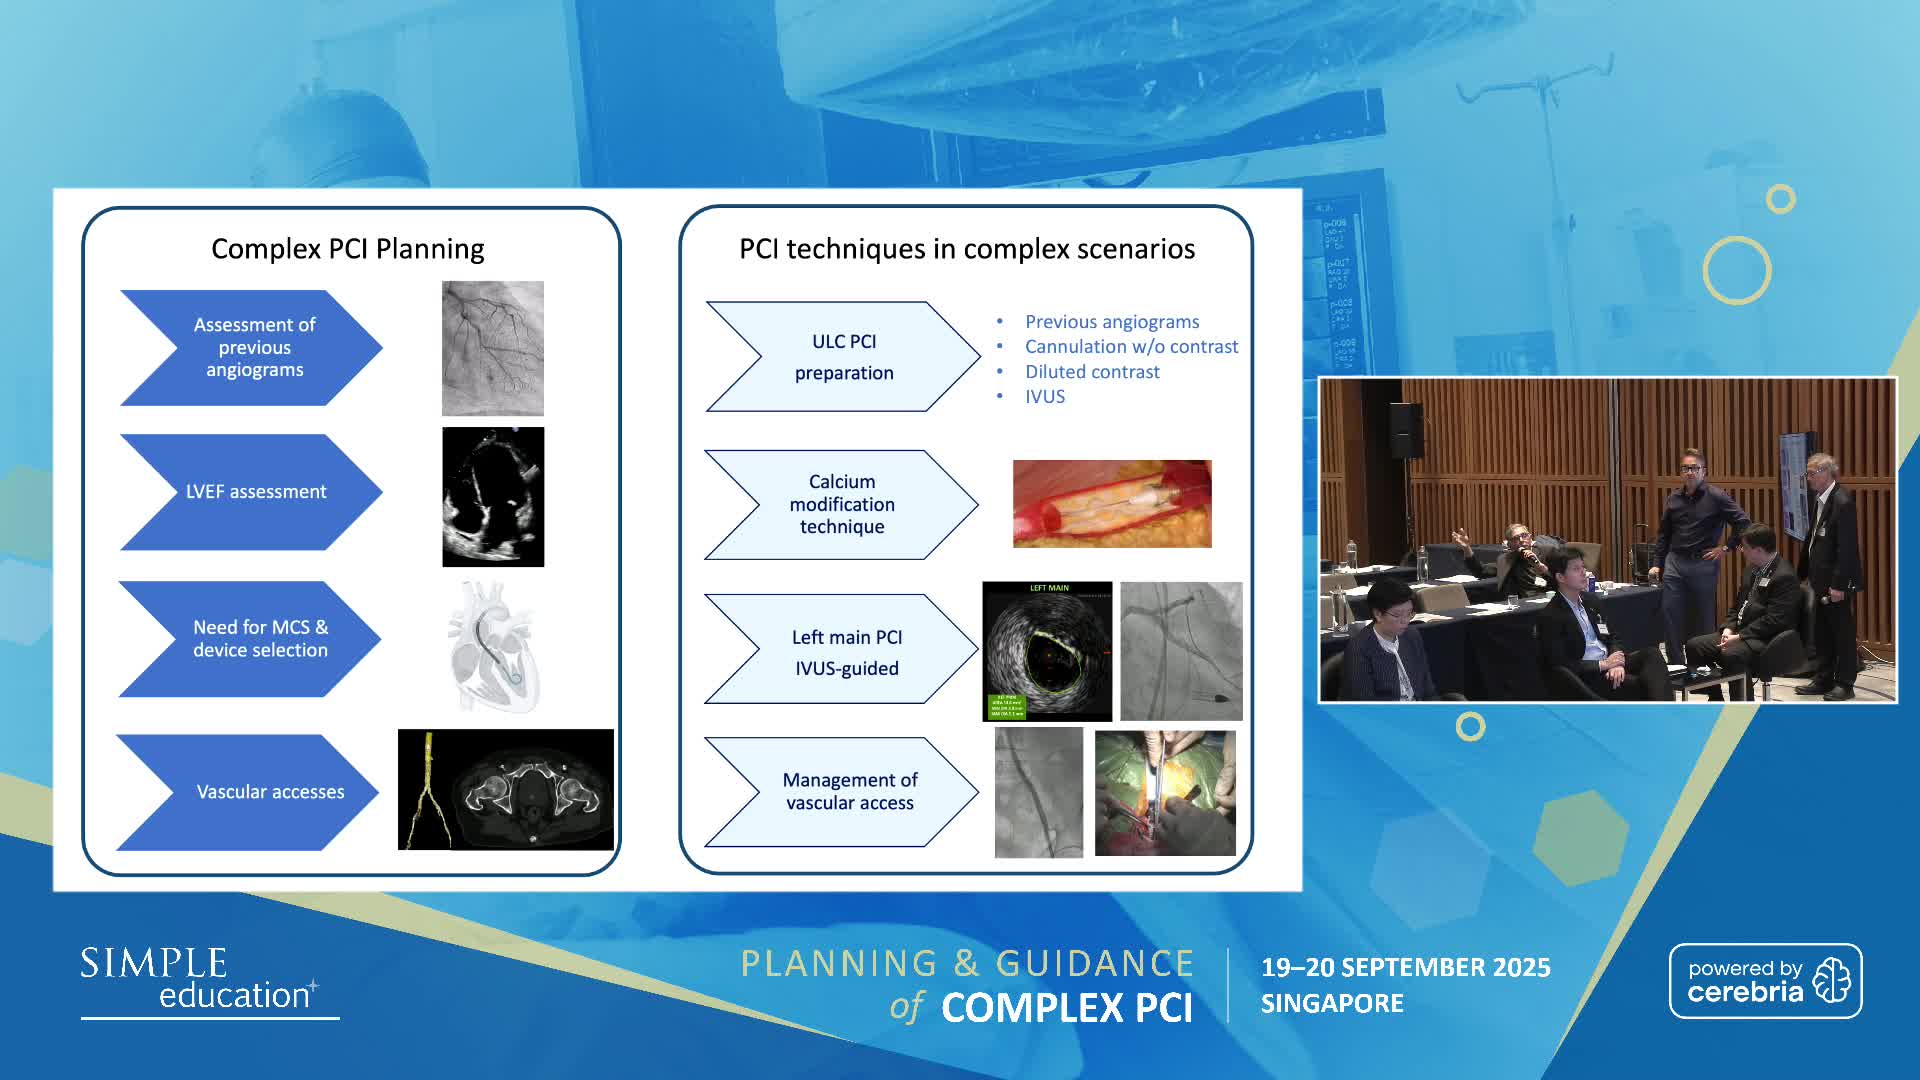

Planning and guidance of complex percutaneous coronary interventions - June 2023 Day One

Planning and guidance of complex percutaneous coronary interventions - June 2023 Day Two

Planning and guidance of complex percutaneous coronary interventions - October 2022 Day One

Planning and guidance of complex percutaneous coronary interventions - October 2022 Day 2

Planning and Guidance of Complex Percutaneous Coronary Interventions - May 2022 Day One

Planning and Guidance of Complex Percutaneous Coronary Interventions - May 2022 Day Two